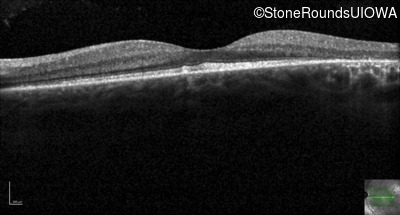

Age at visit: 24 years

OD OS